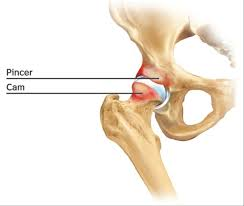

Die häufigsten Ursachen für Hüftschmerzen und Knieschmerzen sind abnutzungsbedingte Veränderungen des Gelenkes sowie auch unfallbedingte Verletzungen  (Knie- und Hüftverletzungen) und Verletzungsfolgen wie beispielsweise Hüftarthrose, Kniearthrose, gelenknahe Knochenbrüche, Meniskusrisse, Kreuzbandrisse.

Behandlungen von Hüft- und Kniegelenksverletzungen und degenerative abnutzungsbedingte Leiden sind eine unserer Spezialitäten, so zum Beispiel Kunstgelenkersatzoperationen an Hüfte und Knie, als auch Knochenbruchbehandlungen insbesondere hüftgelenksnahe Frakturen, Oberschenkelbrüche oder auch Knochenbrüche unter Mitbeteiligung des Kniegelenkes. Eine unserer weiteren Spezialitäten ist die Behandlung von Meniskus- und Kreuzbandrissen. Die Entwicklungen auf diesem Fachgebiet sind enorm vorangeschritten, sodass heute viele Eingriffe in entsprechender arthroskopischer oder minimal-invasiver Technik durchgeführt werden können. Dies führt in der Regel zu bedeutend kürzeren Spitalaufenthalten. Für weitere Informationen wenden Sie sich an unsere Praxis, kontaktieren uns via Kontaktformular oder entnehmen Informationen aus den nebenstehenden Links. Doch was ist eigentlich Arthrose? Lesen Sie auf diesem Link weiter!